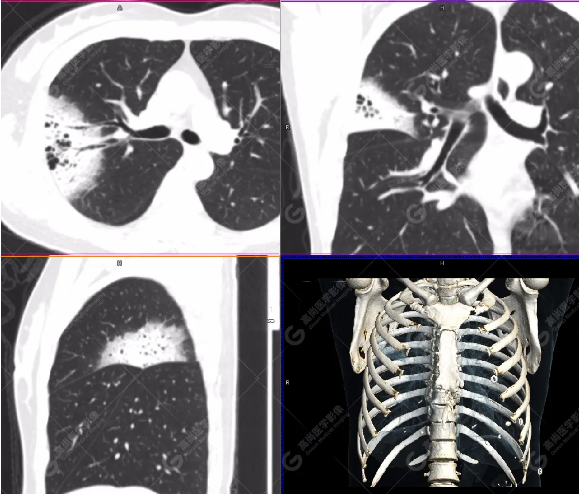

PET/CT影像圖

右肺上葉斑片狀高密度影,部分實(shí)變,邊界清楚,未跨葉間裂;內(nèi)空氣支氣管征、蟲(chóng)蝕樣空洞、周?chē)鷷炚鳎环派湫詳z取增高,SUVmax=4.1。

右肺上葉后段胸膜下片塊狀高代謝病灶,考慮為肺淋巴瘤,請(qǐng)結(jié)合臨床病理。

肺炎實(shí)變型沿支氣管血管束或胸膜下分布片狀高密度影,密度均勻,邊緣模糊,其內(nèi)常見(jiàn)充氣支氣管征或血管造影征,部分見(jiàn)支氣管擴(kuò)張,跨葉生長(zhǎng)常見(jiàn);病理基礎(chǔ):腫瘤細(xì)胞沿支氣管血管束及小葉間隔浸潤(rùn)生長(zhǎng),進(jìn)而出現(xiàn)小葉間隔增厚、支氣管血管束增粗等間質(zhì)性改變,腫瘤細(xì)胞進(jìn)一步破壞肺泡壁、充盈肺泡腔,形成肺內(nèi)實(shí)變影。結(jié)節(jié)腫塊型多位于肺間質(zhì)支氣管旁或胸膜下,多為單發(fā),呈類(lèi)圓形,密度均勻,邊界多清楚、光滑,無(wú)毛刺征,部分周?chē)鷷炚?,?nèi)充氣支氣管征和\或血管造影征;病理基礎(chǔ):支氣管、血管周?chē)[瘤細(xì)胞沿支氣管、血管外周淋巴竇道途徑擴(kuò)散,支氣管、血管、淋巴管周?chē)M織結(jié)構(gòu)增厚,局部形成結(jié)節(jié)或腫塊?;旌闲投喾N影像征象同時(shí)存在,CT表現(xiàn)以實(shí)變、結(jié)節(jié)腫塊為主要征象,合并網(wǎng)狀影、磨玻璃影等間質(zhì)性改變【2】。

空氣支氣管征——特征性表現(xiàn)。病灶內(nèi)見(jiàn)走形自然充氣支氣管影。病理基礎(chǔ):腫瘤細(xì)胞沿著肺間質(zhì)和支氣管黏膜下生長(zhǎng)而支氣管壁不受侵犯,當(dāng)腫瘤細(xì)胞浸潤(rùn)致支氣管周?chē)鷮?shí)質(zhì)破壞和肺泡塌陷時(shí),周?chē)w維組織增生牽拉而導(dǎo)致鄰近支氣管擴(kuò)張,支氣管壁無(wú)破壞。血管造影征——另一特征性表現(xiàn)。增強(qiáng)病灶中肺動(dòng)靜脈形態(tài)、走行自然,無(wú)破壞征象。病理基礎(chǔ):腫瘤組織起源于肺間質(zhì),腫瘤細(xì)胞沿或跨越臟器解剖結(jié)構(gòu)生長(zhǎng),不破壞或侵犯血管壁結(jié)構(gòu),故腫瘤血管豐富,很少出現(xiàn)缺血壞死。暈征、磨玻璃影為本病的常伴征象,但無(wú)特異性,也見(jiàn)于其它疾病,常見(jiàn)于肺部真菌感染。但病理基礎(chǔ)卻不同,前者為腫瘤浸潤(rùn)周?chē)M織使間質(zhì)輕度增厚或氣腔不完全充盈所致,而后者為圍繞侵襲性曲菌病的出血征象【2】。